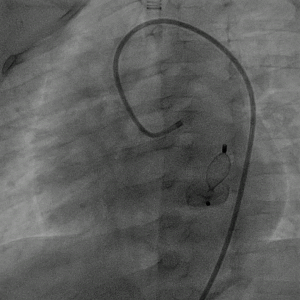

心脏彩超:LV 25 mm,LA 18 mm,RV 11 mm,RA 20 mm;EF 70%,FS 38%。左冠状动脉开口增粗,内径约7 mm,走行迂曲,回旋支增粗,瘘入冠状静脉窦,瘘口径约6 mm,瘘口处频谱呈双期湍流,Vmax=1.6 m/s;冠状静脉窦明显增粗,内径约10 mm,其右房开口径约5.7 mm,频谱呈双期高速湍流,Vmax=5.4 m/s。

图片

心脏彩超